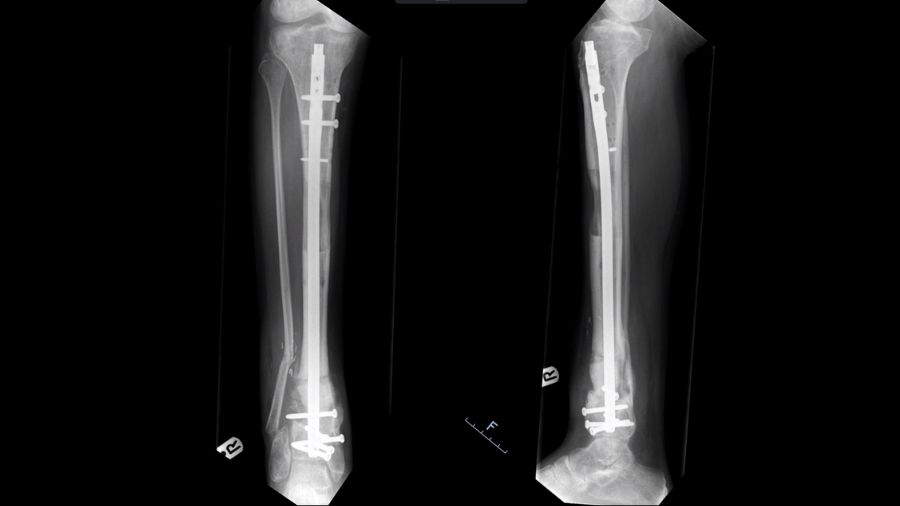

Using lengthening nails in open fractures

The lengthening nail is a new development that could prove to be a game changer and is worth mentioning in this context. It employs the same biomechanics and bone physiology as the Ilizarov method, but with purely internal fixation.

With plate assisted bone segment transport (PABST), a plate holds the limb out to length, which is also what a stacked ring fixator does. In the ring fixator, a middle segment moves to drag the piece of bone down to fill the gap, but here, it’s the lengthening nail that does the moving of the bone. It moves the middle segment from the top to the bottom at the right pace, so that distraction osteogenesis causes new bone to form in the gap. It works in the same way as a frame, but crucially it is not an apparatus on the outside of the leg with the pins dragging through the skin.

A real advantage of this method is that it makes it much easier to deal with swelling, which can be a problem. Because all the stability is internal, patients can wear pressure garments and physiotherapists can get at their leg to help manage the swelling, making the patient journey better.

The transport nails have also reduced the treatment times required. The amount of time spent in the transport phase is reduced because nails can be potentially distracted faster— distraction osteogenesis can happen at a rate of up to 1.25mm a day with fewer breaks for things like pin site infections. You therefore reach the last stage of treatment, managing the docking site, sooner. The patient is still waiting for the fracture to heal and having physiotherapy, but they are not lying in hospital or having to visit as often, which is another improvement. With the lengthening nails, the patient's contact with the hospital and the burden of being a patient is considerably reduced.